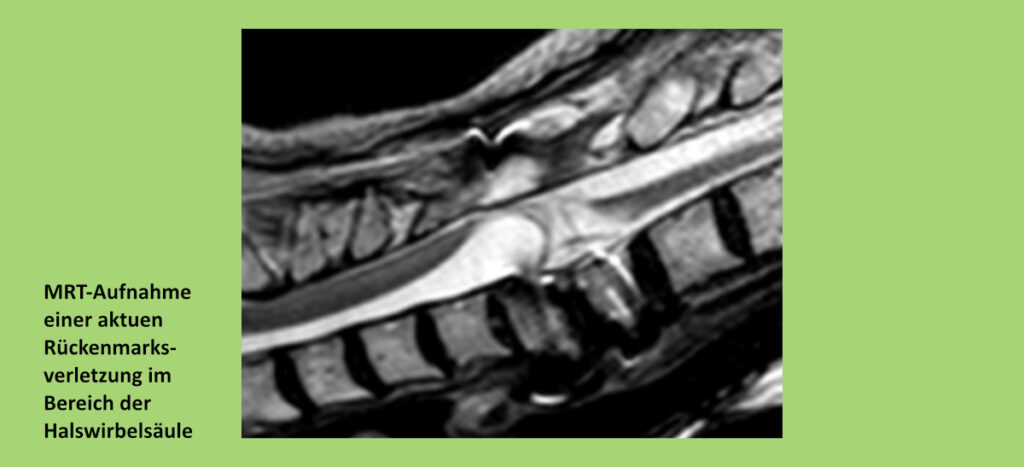

„Wir wollten wissen, ob die Immunschwäche nach einer Rückenmarkverletzung von der Schwere und Höhe der Schädigung abhängt, ähnlich wie es bei einer Lähmung der Muskulatur der Fall ist“, sagt Dr. Marcel Kopp, Wissenschaftler im Bereich Experimentelle Neurologie der Charité. Verursacht wird die Querschnittlähmung durch eine teilweise oder komplette Durchtrennung des Rückenmarks. Unterhalb der Verletzung können die Gliedmaßen gelähmt sein und werden nicht gefühlt. Auch Organe oder Organsysteme können betroffen sein, denn wichtige Nervenverbindungen im Rückenmark sind unterbrochen.